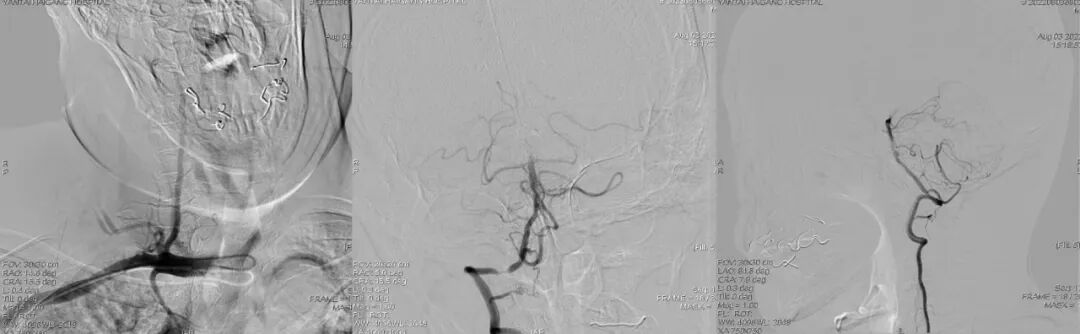

首次DSA 2022.4.9:

导丝怎么扩【载药时代 球扩天下】NOVA DES®颅内药物洗脱支架在椎动脉颅内段重度狭窄的应用二例_https://www.jmylbn.com_新闻资讯_第6张

导丝怎么扩【载药时代 球扩天下】NOVA DES®颅内药物洗脱支架在椎动脉颅内段重度狭窄的应用二例_https://www.jmylbn.com_新闻资讯_第7张

重要影像结论DSA:左侧椎动脉闭塞,右侧椎动脉V4段重度狭窄。